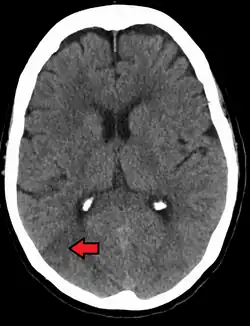

TK głowy pacjenta z PRES, widoczne hipodensyjne zmiany w płatach potylicznych (wskazane strzałką) | |

Tomografia komputerowa ukazuje obrzęk naczyniowy występujący głównie w podkorowej istocie białej płatów potylicznych i skroniowych (choć może występować także w innych częściach mózgowia, takich jak głębiej położonej istocie białej, jądrach podstawnych, ciele modzelowatym czy pniu mózgu[19][27][28]), czasami symetryczny[2][3][5]. Gdy dojdzie do uszkodzenia bariery krew-mózg, zmiany wzmacniają się po podaniu kontrastu gadolinowego[19]. W MRI widoczne są hiperintensywne w sekwencjach T2 i FLAIR zmiany, a obrazy w sekwencji DWI lub ADC czasami mogą pokazywać ograniczenie dyfuzji w obrębie tych zmian[2][3]. W angiografii widoczne jest obkurczenie naczyń mózgowych[2][19].